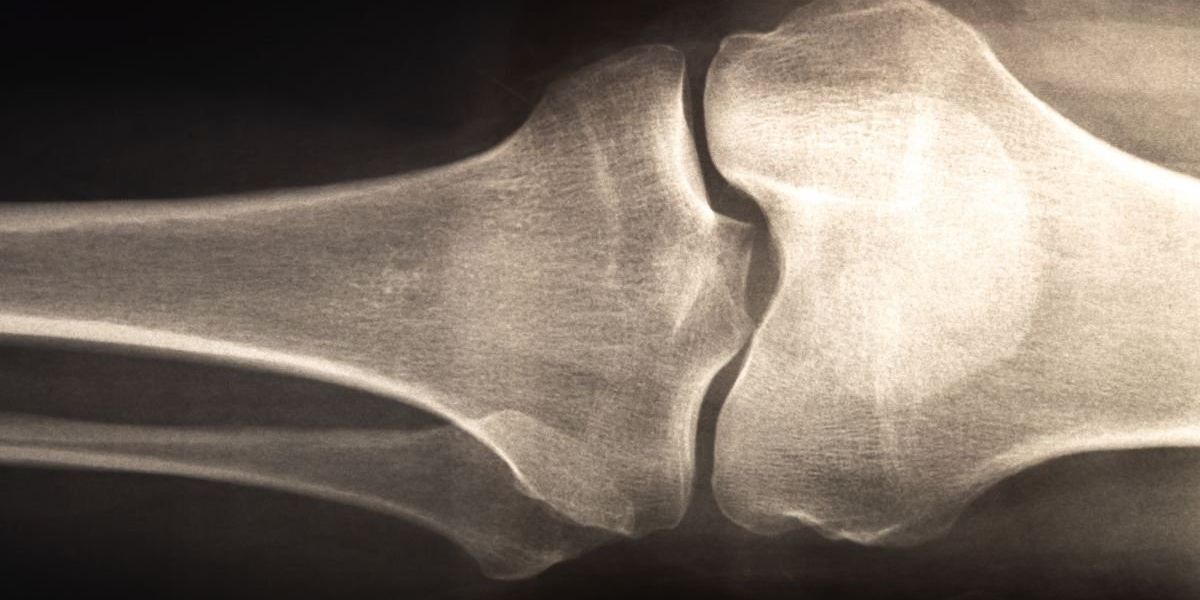

Age-old diet linked to lower risk of bone fractures in study

Osteoporosis: Age-old diet linked to lower risk of bone fractures in study`;